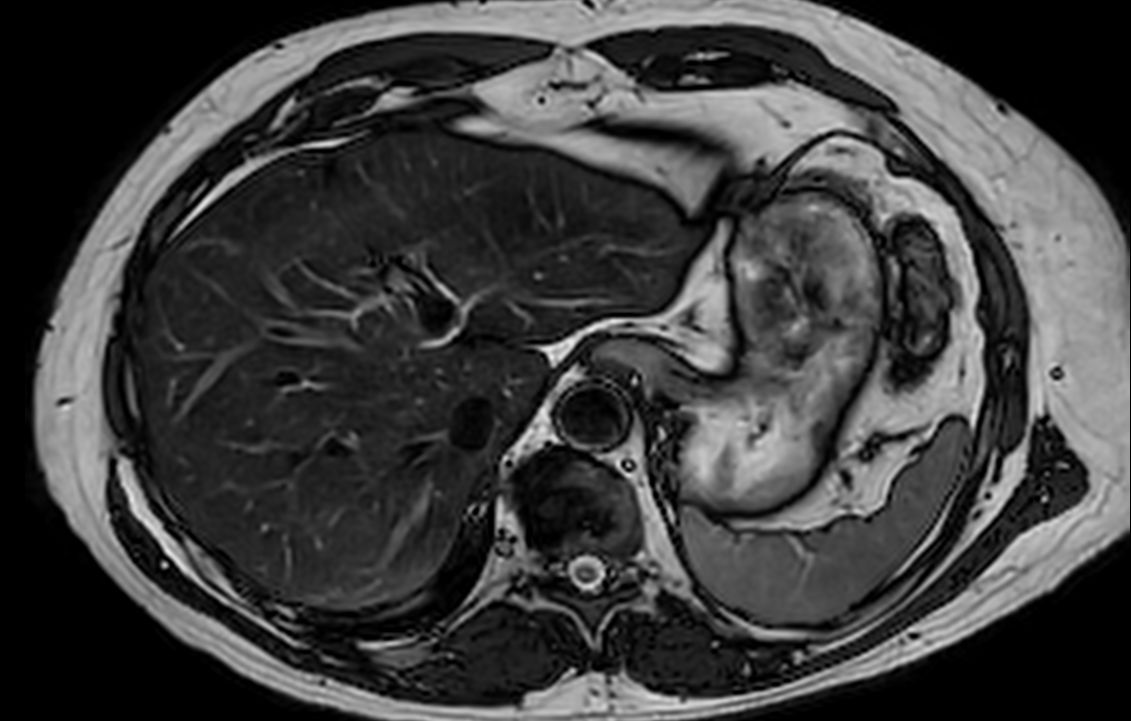

Liver imaging case, leveraging Philips SmartSpeed, our breakthrough new MRI application that delivers image and speed without compromise. Building on our proven technology and leveraging AI* to take fast MRI technology to the next level. Imaging speed is increased while providing greater resolution to deliver outstanding image quality. It covers motion imaging, free-breathing imaging and diffusion-weighted imaging to address the needs of a broad range of patients in various conditions.

Axial T2w TSE mDIXON (in-phase)SmartSpeed MotionFree